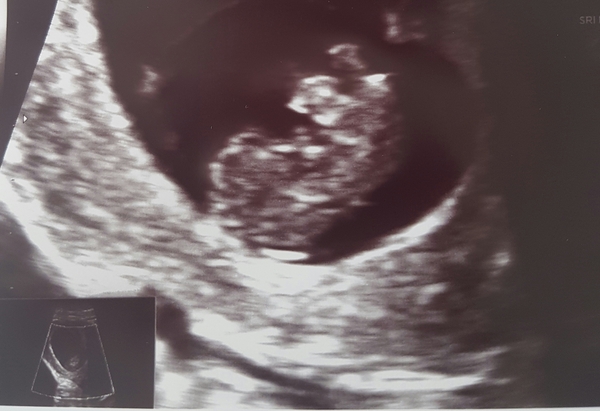

It's good news!! Baby is healthy and happy and measuring exactly as he/she should be!! Yay!! I couldn't believe they actually let me listen to the heartbeat too, I thought it was too early but there it was chugging away 😆 I attached a picture they gave me of baby doing a head stand to show off for us! 💓💓💓 amazing! Wahoooo oolong 😆

Brilliant news Lynsey! What is baby measuring? That is a lovely pic!

Baby measuring 22mm lol. By the measurements they had it was coming up 8+6 but she said we'll stick to my dates which is 8+3 with the early scans not being super accurate.

I think 8+6 will end up being more accurate. My scan at 8+3 was much more splodge like! Your little bean looks like a baby!!! I was moved forward then from 7+5 to 8+3 and at my scan yesterday I was moved forward again from 11+1 to 11+4. That means my due date has gone from 27th of January to the 20th! I guess, because I know when I ovulated, baby must have raced down my fallopian tube and implanted quickly! It also explains why I got 2-3 on a CBD when I thought I could only have been 1-2 at most!

Whatser Your post has made me feel even better! Glad you think he/she looks like a baby lol. Could definitely see arm and leg buds! I certainly don't mind being moved on a few days, I was dreading them putting me back. Now it means I'm nearer 9 weeks which is when the nausea etc is ment to be at its peak. So hopefully I'll start getting past the worst ready for the summer holidays...3 boys at home for 6 weeks 😲